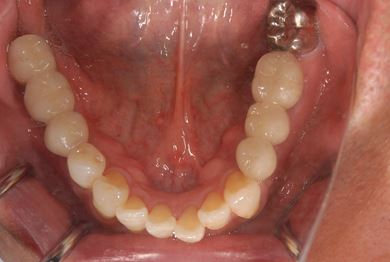

抜歯即日スピードインプラント治療

| 性別/年齢 | 男性 / 65歳 | ||||||||||||||||||||||||||||||||

| 主訴 | 右奥歯の義歯の不具合について相談したい。 | ||||||||||||||||||||||||||||||||

| 治療方針 | 抜歯と同時にインプラント埋入を行い、治療期間を短縮する。 | ||||||||||||||||||||||||||||||||

| 治療内容 | インプラント5本(抜歯即日スピードインプラント、テンポラリーインプラント)、メタルボンドセラミッククラウン5本 | ||||||||||||||||||||||||||||||||

| 総治療費 | 1,913,100円 | ||||||||||||||||||||||||||||||||

| 治療期間 | 1年9ヶ月 |